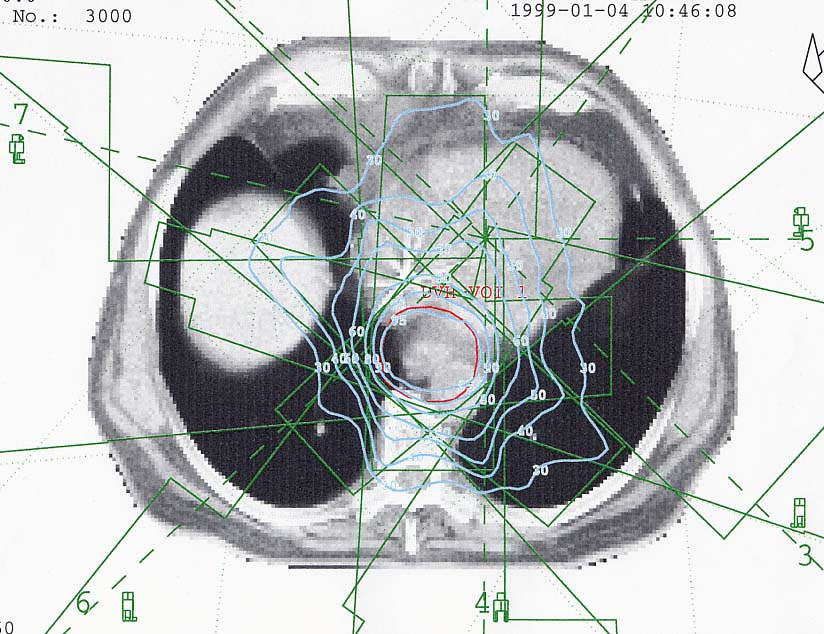

Tumore des Magens: Bestrahlungsplan

Bestrahlungspläne